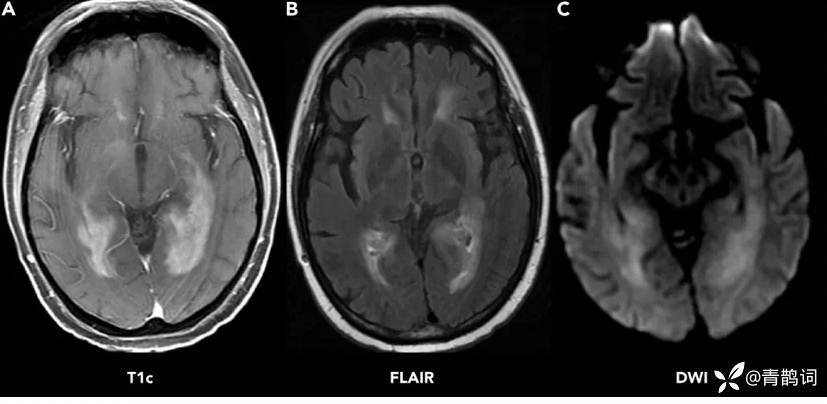

(A)T1序列显示深部白质的均匀增强病变;(B)FLAIR序列显示病变周围有中度水肿;(C)DWI显示病变内弥散受限

MR平扫肿瘤在T2WI上信号常常接近或略低于脑白质信号,可见弥散受限。

MR增强呈明显均匀强化,部分病灶可出现 典型的脐凹征、尖角征、蝶翼征。